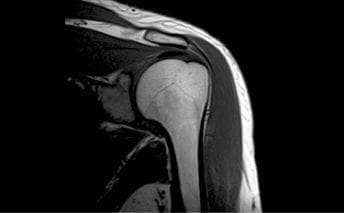

MRI(磁気共鳴画像撮影装置)

人間の身体、その7割は水(H2O)です。MRIは磁気を使って、水の中の「水(H)」の動きをとらえて、組織の様子を画像化します。

- 特長

- 脂肪、筋肉、骨、腱などが明瞭に観察でき、骨盤内の描出に優れている